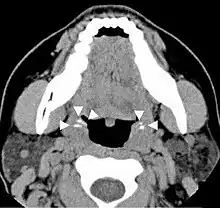

Diagnosis is usually made upon inspection. Tonsilloliths are difficult to diagnose in the absence of clear manifestations, and often constitute casual findings of routine radiological studies.

Imaging diagnostic techniques can identify a radiopaque mass that may be mistaken for foreign bodies, displaced teeth or calcified blood vessels. CT scan may reveal nonspecific calcified images in the tonsillar zone. The differential diagnosis must be established with acute and chronic tonsillitis, tonsillar hypertrophy, peritonsillar abscesses, foreign bodies, phlebolites, ectopic bone or cartilage, lymph nodes, granulomatous lesions or calcification of the stylohyoid ligament in the context of Eagle syndrome (elongated styloid process).[11]